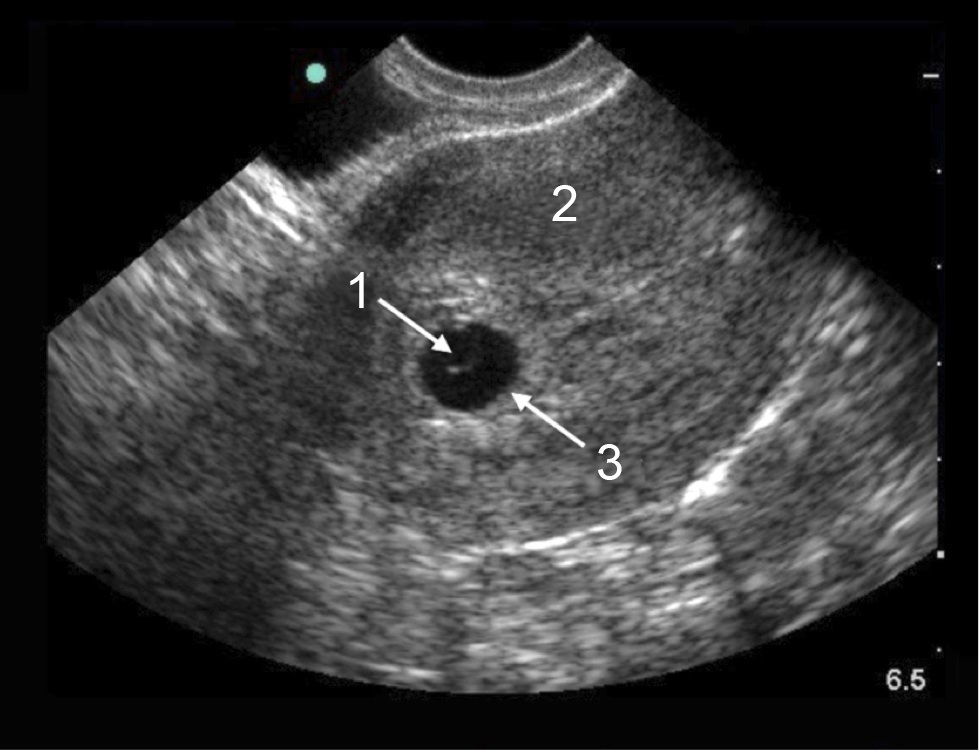

Pelvic Endovaginal – Early Gestational Sac with Yolk Sac Image

Yolk Sac

Uterus

Gestational Sac